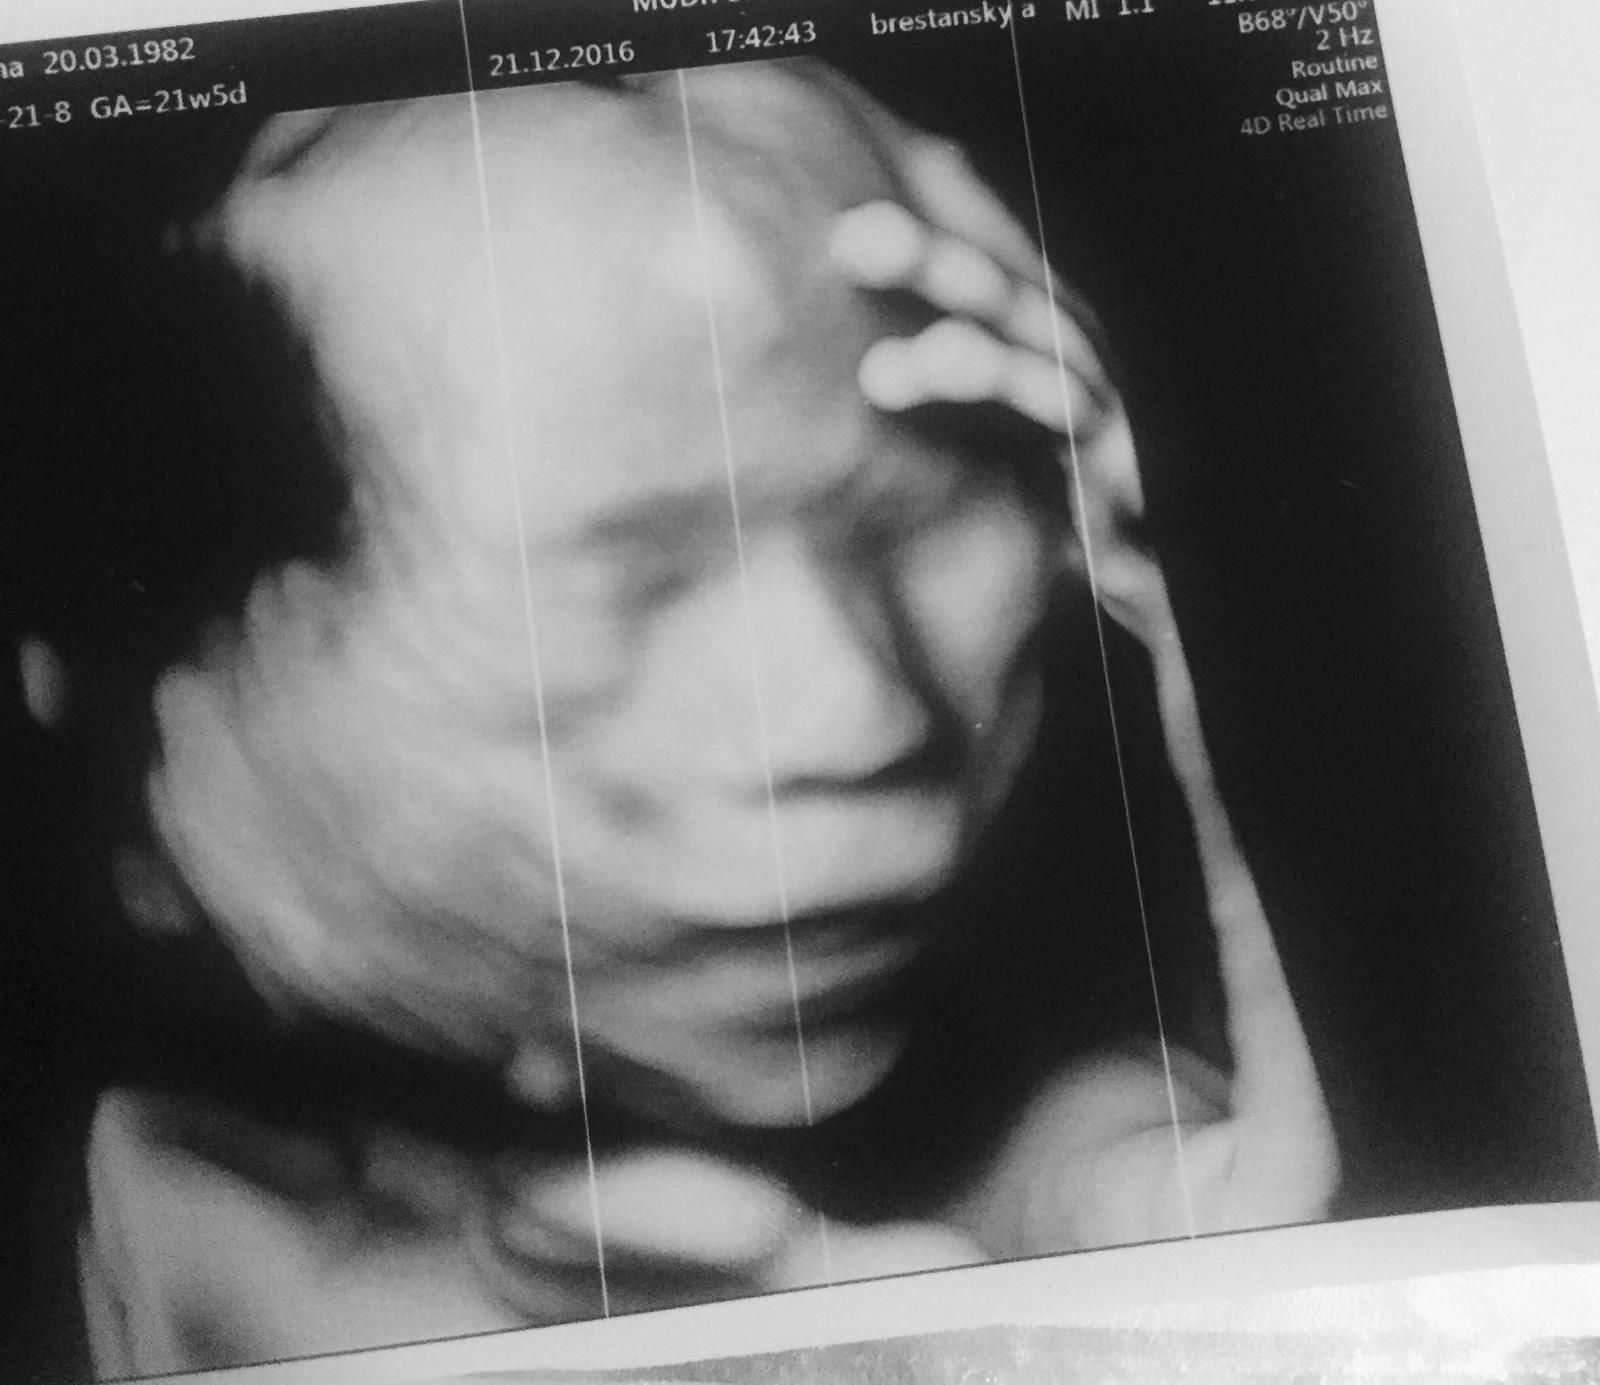

Ahojte, tak uz mam poradnu zasebou. Vsetko je v poriadku. Som 12tt+1 podla USG. Malicke je 56,1mm velke a veeelmi aktivne. Odbery mi budu robit az 18.1. a vtedy dostanem aj teh.knizku. Mam len trocha vyssi tlak preto mi dal magne b6. Spominal mi iba kombinovany test, ktory najblizsie robia v Ke.